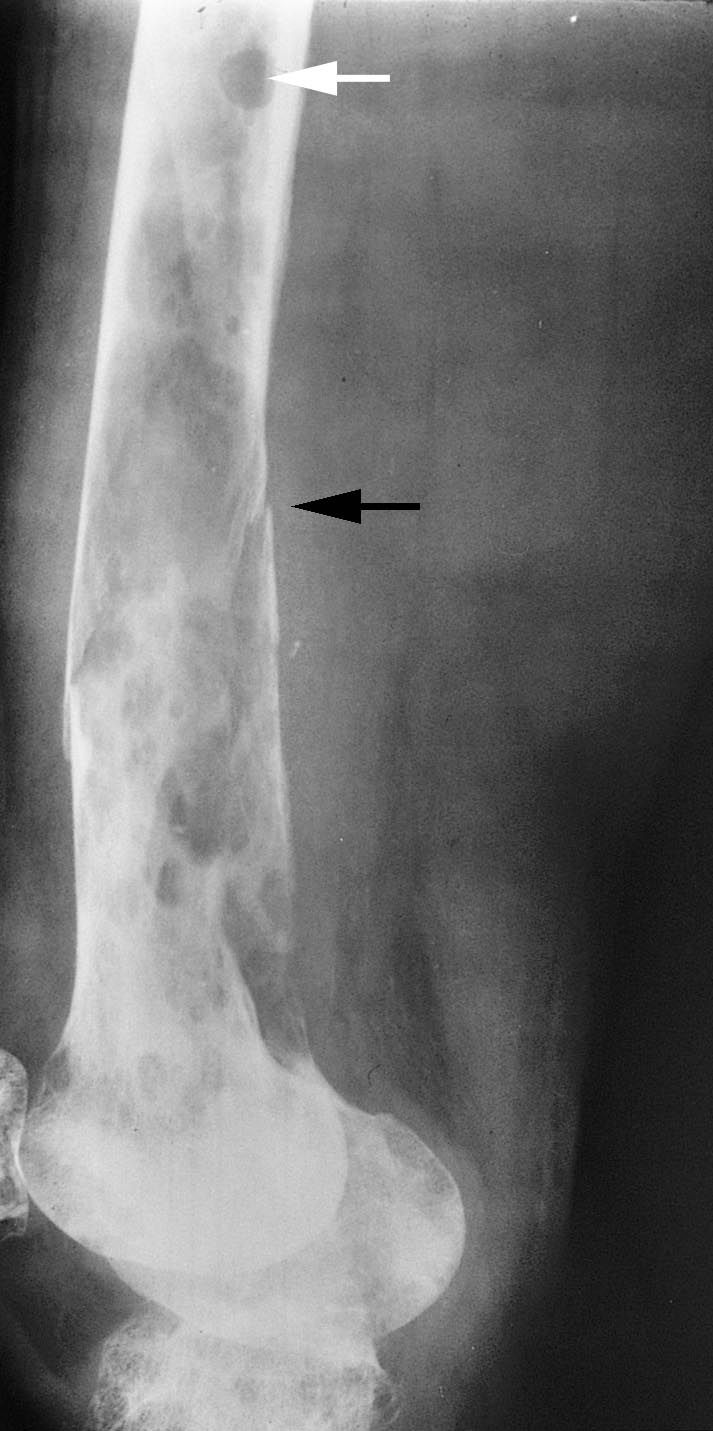

X-rays of multiple myeloma and a pathologic fracture

This X-ray, taken from the side, shows the lower end of a patient’s femur near the knee. Multiple myeloma has weakened the bone and resulted in a pathologic fracture (black arrow). The white arrow is pointing at one of the “punched out” holes typically seen on X-ray.

Reproduced from Johnson TR, Steinbach LS (eds.):  Essentials of Musculoskeletal Imaging. Rosemont, IL. American Academy of Orthopaedic Surgeons, 2004, p. 145.